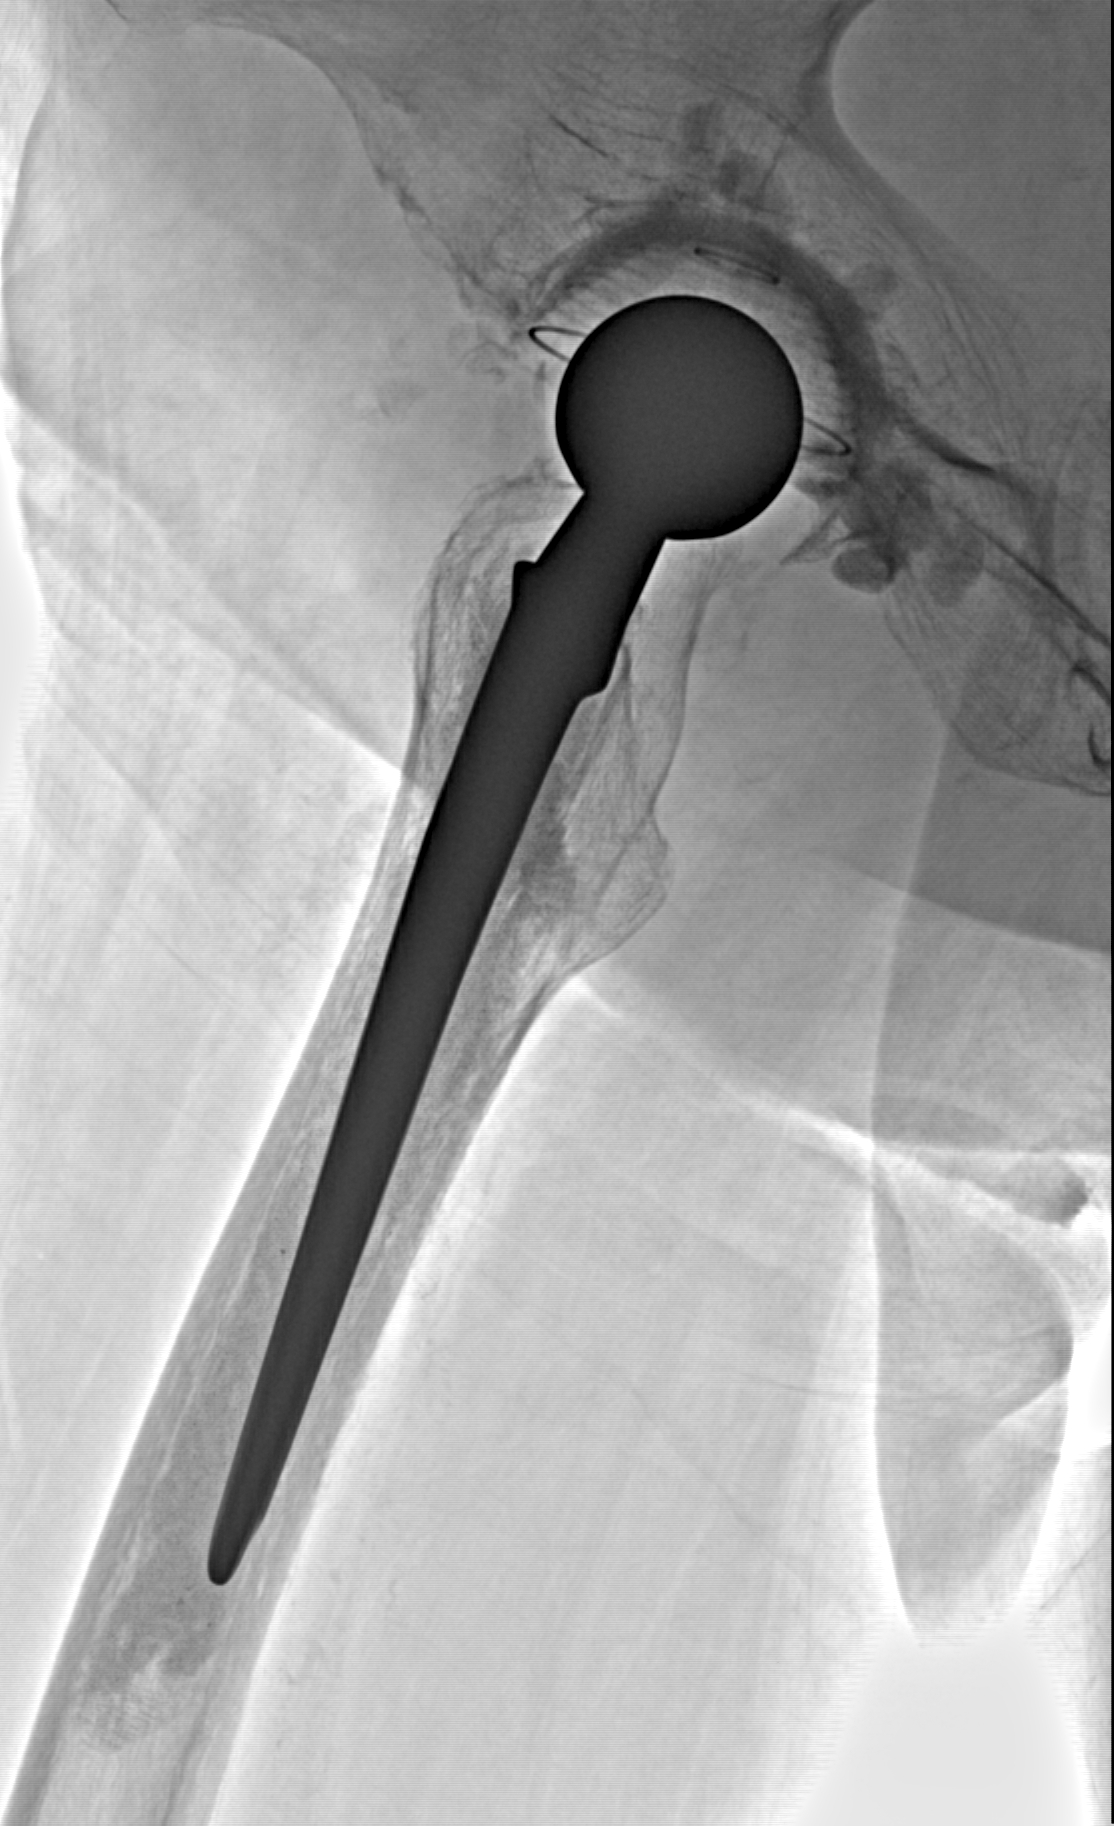

Эндопротез

Рентгенограммы

Рентген на дому: по вашему адресу приезжает врач-рентгенолог, травматолог-ортопед с мобильным рентгеновским аппаратом, проводит диагностику травмы или заболевания, делает необходимые рентгенограммы, дает рекомендации по дальнейшему лечению. Получить качественные снимки в домашних условиях возможно благодаря уникальной методике, разработанной МосРентген Центром для института  Склифосовского